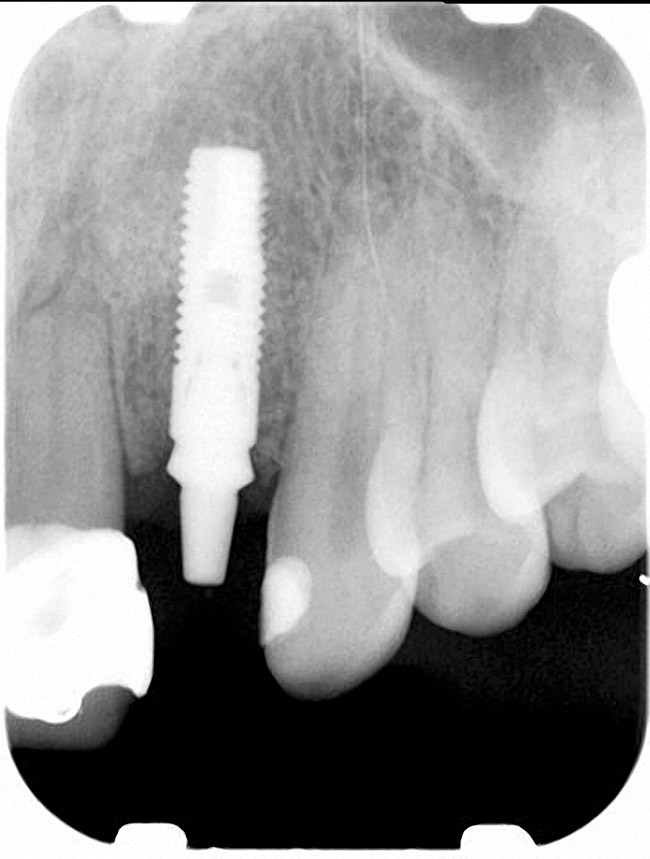

Figure 4 Characterization of the interproximal bone and tooth contacts: A periapical radiograph assists in measuring the distance from bone crest to the adjacent tooth contact points for missing tooth No. 8. The mesial bone crest to the adjacent tooth con

Figure 4

Figure 5 Characterization of the interproximal bone and tooth contacts: A periapical radiograph assists in measuring the distance from bone crest to the adjacent tooth contact points for missing tooth No. 8. The mesial bone crest to the adjacent tooth con

Figure 5